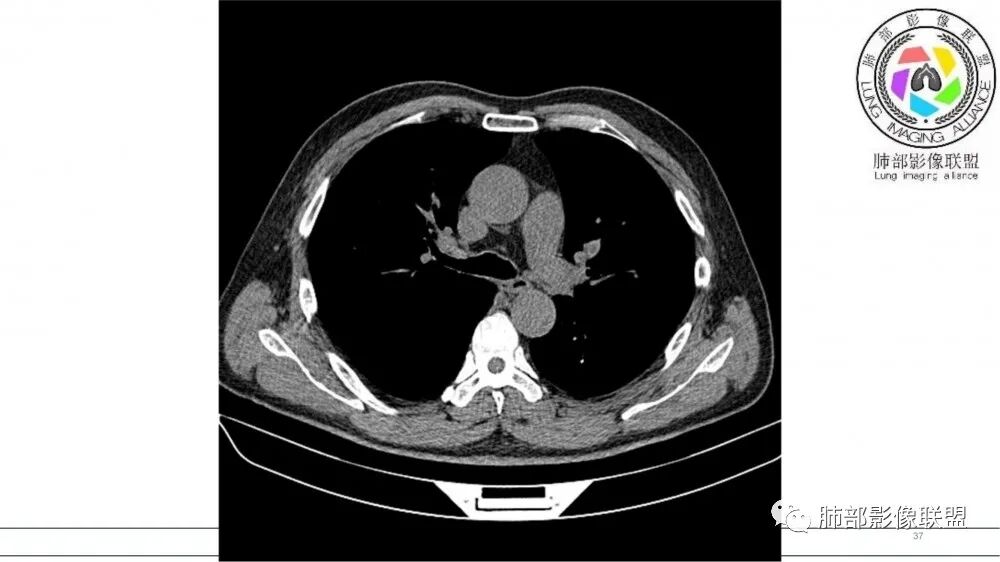

老年男性,术前检查肺气肿背景,左肺上叶结节,沿支气管蠕虫样生长,左肺门及纵隔淋巴结肿大,增强扫描不均匀强化,血管包绕,结合吸烟史,考虑小细胞肺癌。

老年吸烟男性,尖前段支气管内塑形生长,增粗蠕虫样,没有肺不张(排除鳞癌?),远端少许阻塞肺炎,增强低强化,锁定小

老年男性,吸烟,指套征,蠕虫征,阻塞性炎症不严重。可见血管穿行,密度均匀,轻度强化,首先考虑小细胞肺癌。鉴别鳞

2021年8月6日晨读病例结果:小细胞肺癌

指套征:是影像征象,胸部平片表现为手指状密度增高影,以肺门为中心呈放射状分布,CT显示扩张支气管内低密度黏液栓形成或实性病变,呈管状、树枝状或卵圆形密度增高影;支气管扩张伴近端梗阻时,扩张支气管内部黏液分泌物不能排出而形成。可以伴随远端空气潴留征、阻塞性炎症。

按照肿瘤发生部位,SCLC 主要有中心型与周围型。

研究报道,中心型 SCLC 经 CT 扫描后通常支气管表现为鼠尾样狭窄,肺门或纵隔肿块明显,由于肿块沿管壁生长表现为顺延支气管形态的不规则形状。病灶相对特征性影像学表现比如鸭蹼状、腊肠状、葫芦状及葡萄状改变,可以出现血管包埋,很少有空洞、空泡,较少引发肺不张,阻塞性炎症成都较轻。与一般肺癌比较,恶性程度高,侵袭力强、病灶很小就容易远处转移!Herzberg 等[19]研究指出,20%以上 SCLC 倍增时间短,预后不良。

文献报道周围型小细胞肺癌发生率为全部小细胞肺癌类型的 35%,近来有学者认为周围型病灶发生率可能更高。CT检查表现为肺实质结节或团块状,密度多较均匀,表现为浅分叶状,边缘光滑、锐利而有时可以酷似良性肿瘤。毛刺征、胸膜凹陷征与空洞、钙化少见,周围血管集束征表现为阴性,出现推移让位等情况。文献报道,增强扫描周围型肿块常表现为“沼泽地样”轻中度强化,增强后密度较低略为均匀,出现小片稍低模糊坏死 。